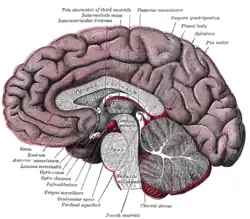

Drawing of a cast of the ventricular cavities, viewed from the side. | |

MRI section of mid-brain. Median sagittal section of brain.

Median sagittal section of brain. Scheme showing relations of the ventricles to the surface of the brain.